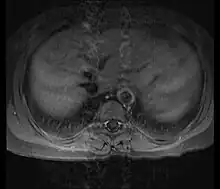

Although the cause of Takayasu arteritis is unknown, the condition is characterized by segmental and patchy granulomatous inflammation of the aorta and its major derivative branches. This inflammation leads to arterial stenosis, thrombosis, and aneurysms.[3] There is irregular fibrosis of the blood vessels due to chronic vasculitis, leading to sometimes massive intimal fibrosis (fibrosis of the inner section of the blood vessels).[5] Prominent narrowing due to inflammation, granuloma, and fibrosis is often seen in arterial studies such as magnetic resonance angiography (MRA), computed tomography angiography (CTA), or arterial angiography (DSA).

Diagnosis is based on the demonstration of vascular lesions in large and middle-sized vessels on angiography, CT scan, magnetic resonance angiography or FDG PET.[11] Seeing abnormal diffuse arterial wall thickening, the 'macaroni sign', with ultrasound is highly suggestive of the condition.[12] FDG PET can help in diagnosis of active inflammation not just in patients with active Takayasu arteritis prior to treatment but also in addition in relapsing patients receiving immunosuppressive agents.[4][13]

Contrast angiography has been the gold standard. The earliest detectable lesion is a local narrowing or irregularity of the lumen. This may develop into stenosis and occlusion. The characteristic finding is the presence of "skip lesions," where stenosis or aneurysms alternate with normal vessels. Angiography provides information on vessel anatomy and patency but does not provide information on the degree of inflammation in the wall.[11]